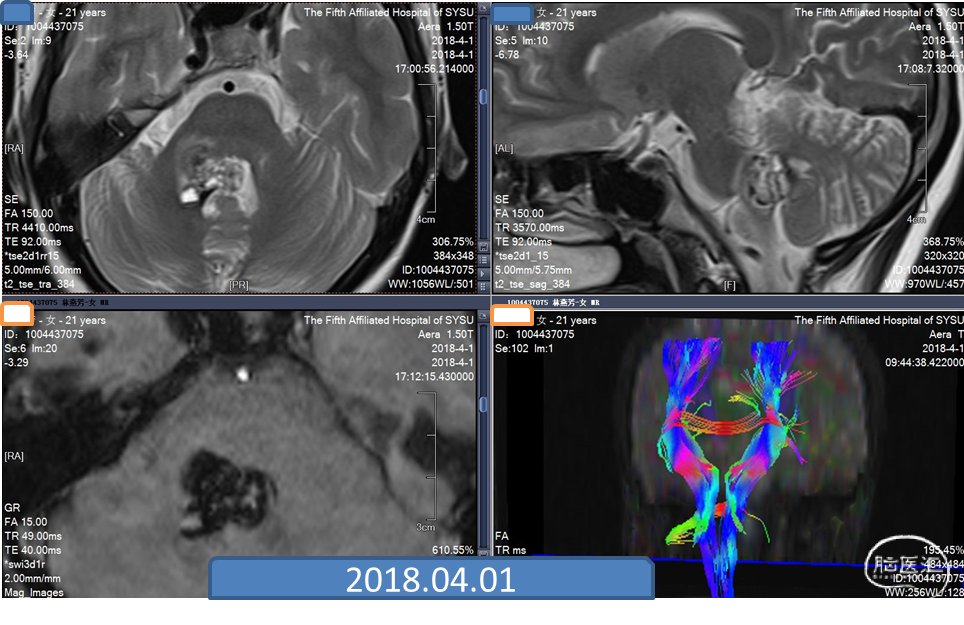

脑干海绵状血管瘤是一种多发的海绵状血管瘤。患者于2017年发现海绵状血管瘤,2018年由于反复出血做手术,手术效果好。2020年11月,患者头痛并有出血症状。2020年12月再次出血,第二次手术。复查CT,情况良好。